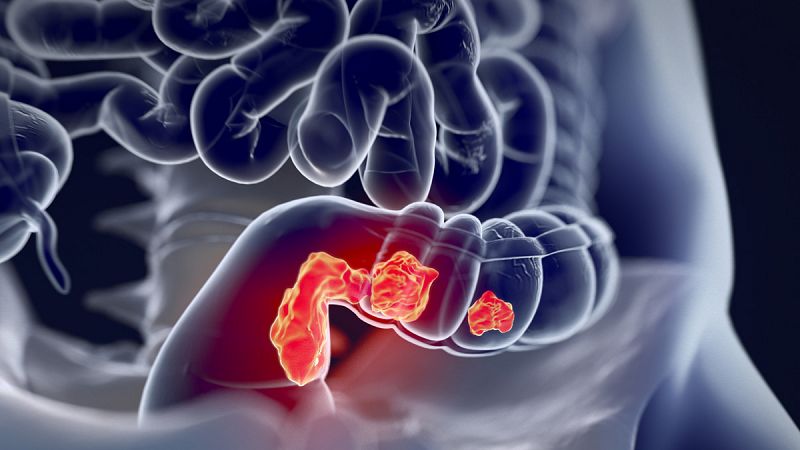

- Expertos apuestan por un abordaje personalizado y multidisciplinar del tumor

- También por cirugías menos agresivas que garanticen la misma supervivencia

- Programas de cribado con mamografía han incrementado el diagnóstico precoz

- Los casos de personas que rondan los 50 años se han incrementado

- Se debe a que los hombres se hacen más pruebas y atienden a síntomas leves

- El 90% de los diagnósticos se produce en fases precoces